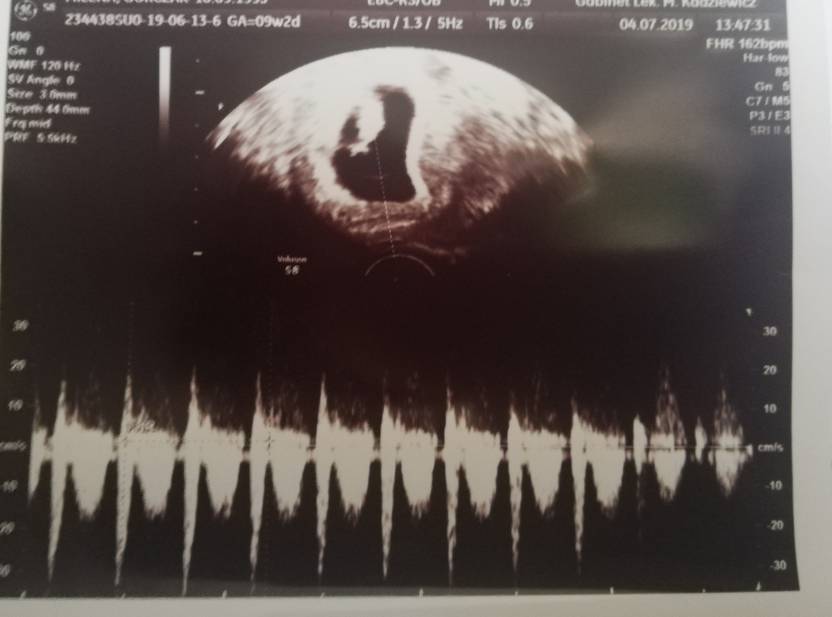

Cześć Dziewczyny przedstawiam Wam mojego maluszka ma 2.20 cm i nawet pomachał nóżkami na USG [emoji6] jak na razie jest wszystko idealnie aczkolwiek dostałam luteine na miesiąc. No i od dzisiaj jestem na L4 [emoji6] trzymam kciuki za resztę [emoji3526]Zobacz załącznik 994175Zobacz załącznik 994176